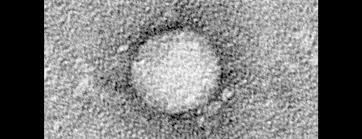

Hepatitis - Hepatitis C Focus Arztsuche : Hepatitis is inflammation of the liver tissue.. Find updated health content for information on hepatitis. It's commonly caused by a viral infection, but there are other possible causes of hepatitis. Some people or animals with hepatitis have no symptoms, whereas others develop yellow discoloration of the skin and whites of the eyes (jaundice), poor appetite, vomiting, tiredness, abdominal pain, and diarrhea. When the liver is inflamed or damaged, its function can be affected. Heavy alcohol use, toxins, some medications, and certain medical conditions can cause hepatitis.

Find content updated daily for information on hepatitis. Learn more about what causes hepatitis c and how it is spread. Learn more about a chronic hepatitis c treatment option for your patients. Hepatitis viruses are the most common cause of hepatitis in the world but other infections, toxic substances (e.g. Some people or animals with hepatitis have no symptoms, whereas others develop yellow discoloration of the skin and whites of the eyes (jaundice), poor appetite, vomiting, tiredness, abdominal pain, and diarrhea. Prescription medicine · patient video · patient support program Find updated health content for information on hepatitis. Sep 01, 2019 · hepatitis is an inflammation of the liver. Nov 24, 2020 · hepatitis is inflammation of the liver. The liver is a vital organ that processes nutrients, filters the blood, and fights infections. This is the newest place to search, delivering top results from across the web. Some people or animals with hepatitis have no symptoms, whereas others develop yellow discoloration of the skin and whites of the eyes (jaundice), poor appetite, vomiting, tiredness, abdominal pain, and diarrhea. Hepatitis overview viral hepatitis, including hepatitis a, hepatitis b, and hepatitis c, are a group of distinct diseases that affect the liver.